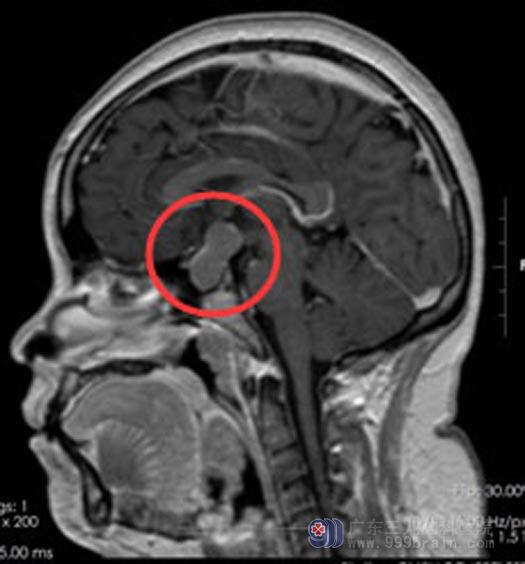

在广东三九脑科医院垂体瘤诊疗中心,由鲁明副院长主刀,实施“经鼻蝶鞍区占位切除术”,手术过程顺利。

▲手术前